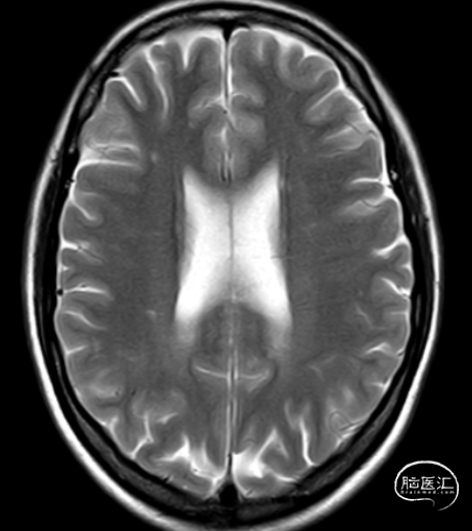

头颅MRI平扫

头颅MRI+MRA提示

6、脑白质病变。